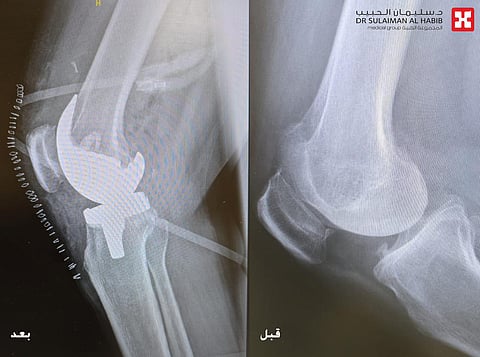

والذي أضاف بأنه عند وصول المراجعة للمستشفى قادمة من مدينة الطائف، تم الإستماع إلى شكواها والإطلاع على ملفها الطبي وإجراء الفحص السريري، وتبين أنها تشكو من ألم حاد في الركبتين يعيق حركتها مع وجود انتفاخ شديد بالمفصلين، وأن قدرتها على المشي لا تزيد عن دقائق محدودة، بالإضافة إلى شعورها بالإزعاج الشديد أثناء النوم. موضحاً أن فحوصات الأشعة السينية الرقمية (Digital X-rays) والتحاليل المخبرية، كشفت عن إصابتها بخشونة شديدة في مفصلي الركبة من الدرجة الرابعة واحتكاك العظم عند المشي، وهو الأمر الذي نتج عنه شعورها بالآلام الشديدة.

مؤكداً على أنه تم وضع خطة علاجية تتضمن التدخل الجراحي العاجل لإنهاء نوبات الألم، وذلك عبر فريق طبي مكون من الدكتور سعود المسلماني استشاري جراحة العظام وأطباء التخدير والتمريض والعلاج الطبيعي، وعقب الإنتهاء من اتخاذ كافة التدابير اللازمة لصحة وسلامة المراجعة، تم إخضاعها لعملية جراحية دقيقة استغرقت 3 ساعات ونصف تحت التخدير العام، وتم فيها استبدال مفصلي الركبتين بمفاصل صناعية متطورة مصنوعة من مادة الكوبالت كروم، وهي من أكثر المفاصل الصناعية نجاحاً واستخداماً بالعالم، والتي تتميز بالعمر الطويل وإعطاء أعلى مدى للحركة بعد العملية، بحيث أن المراجعة تستطيع المشي والصعود والهبوط من الدرج.